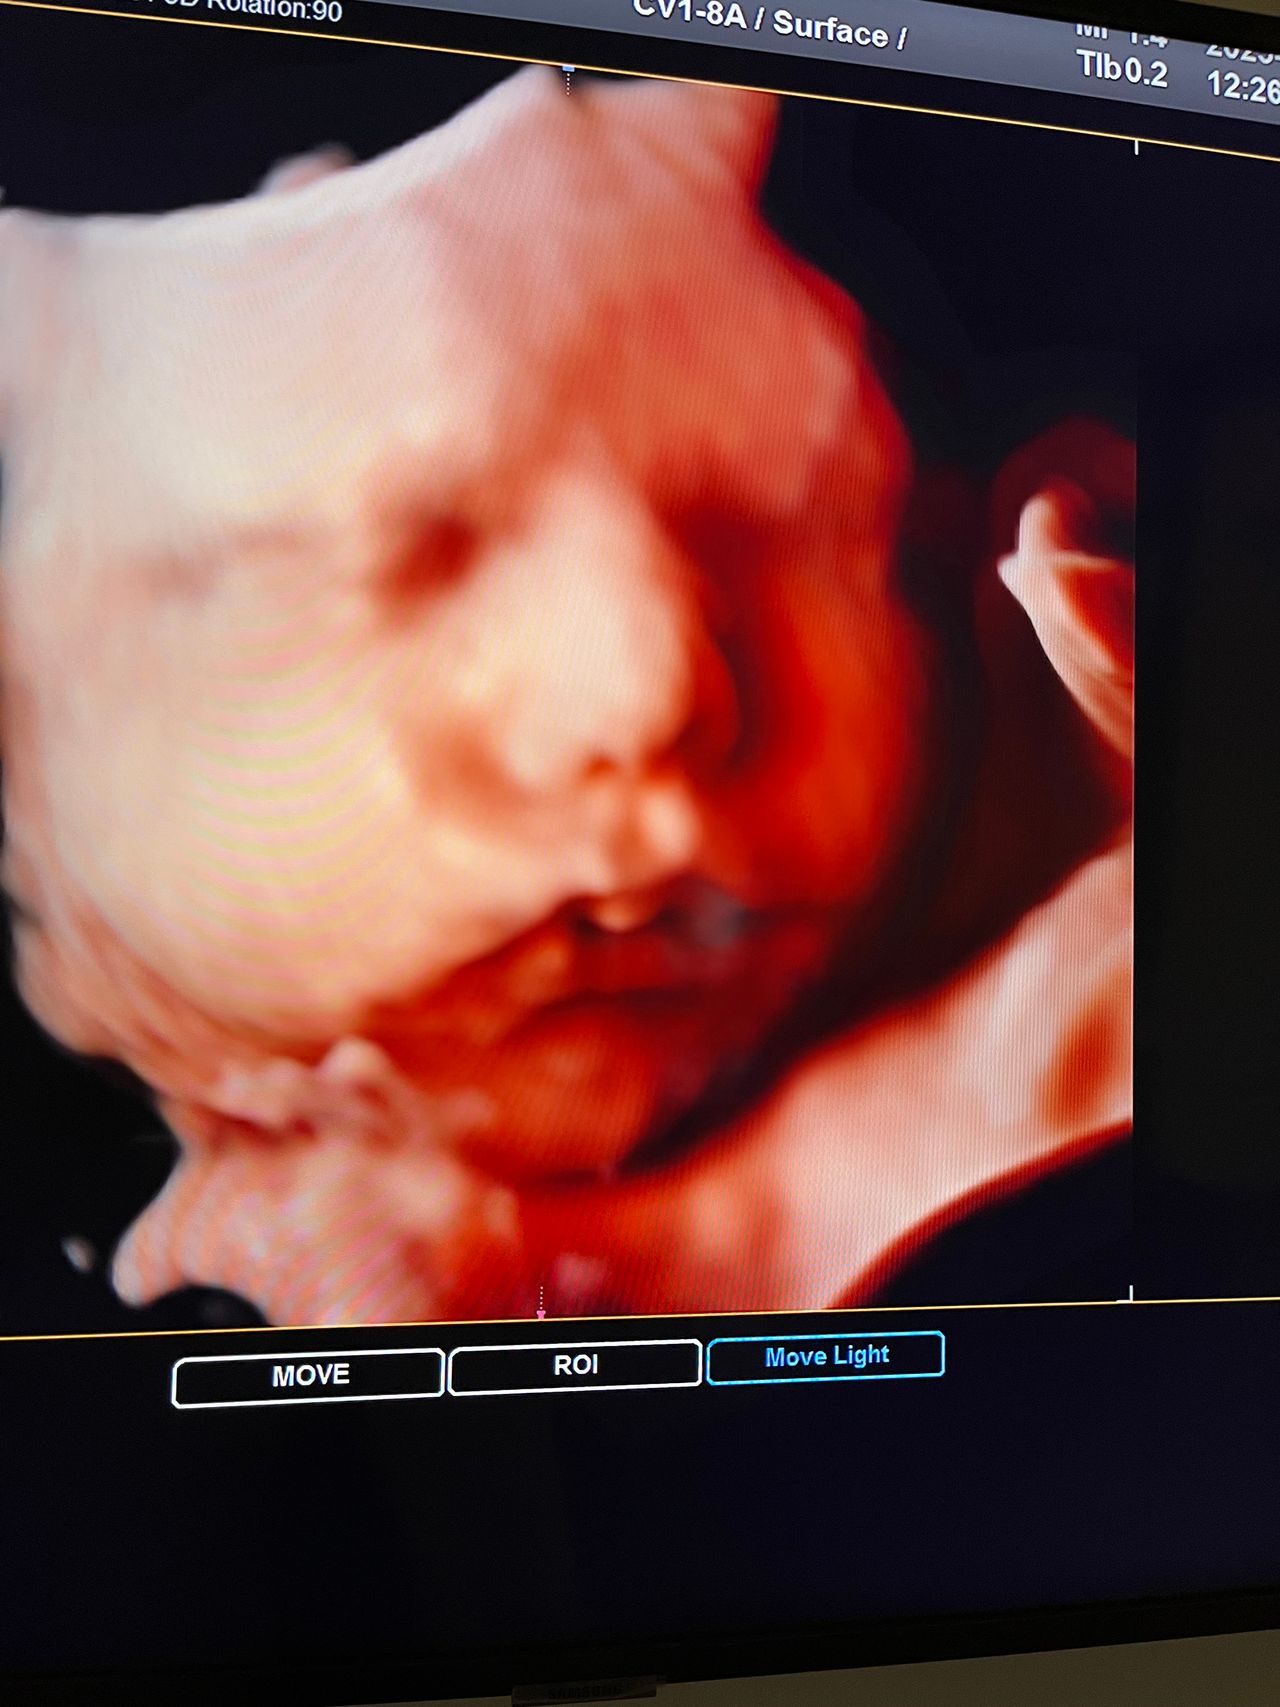

Attualmente lavoro come Dirigente medico nella SC di Ostetricia e Ginecologia dell'Ospedale Michele e Pietro Ferrero di Verduno, mi occupo prevalentemente di screening prenatale, ecografia ostetrica del I trimestre( misurazione translucenza nucale,NT), ecografia morfologica del II trimestre, ambulatorio pregresso taglio cesareo, ecografia ostetrica 3D. Seguo le gravidanze fisiologiche e quelle ad alto rischio , presto servizio in sala parto. Eseguo visite ginecologiche di I-II livello in regime ambulatoriale, counseling contraccettivo ed eventuale prescrizione pillola, inserimento spirale (IUD), dispositivo sottocutaneo (Nexplanon).

Foto e video